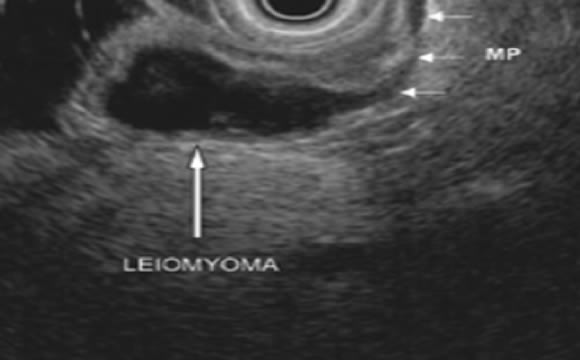

Yemek borusu, mide ve ince bağırsak duvar yapısı 5 katman halinde gözlenir. Katman yapısı ve duvardan kaynaklanan tümöral yapıların derinliği belirlenir.

Üst sindirim sistemi komşuluğunda olan organlar , yani pankreas, safra kesesi ve safra kanalları endoskopik ultrason ile çok net olarak gözlenir ve bu organlardan parça alınabilir. Yine lenf düğümleri, tümörler, kistler ve kan damarları bu incelemeler esnasında incelenir ve gerekirse ince iğne aspirasyonu yapılır. Bu şekilde doku tanısı konulabilir.